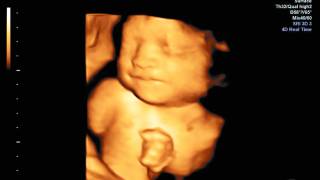

Buscan que ultrasonido detecte partos prematuros

CUERNAVACA, MORELOS.- En el recién creado Laboratorio de Ultrasonido Médico del Instituto de Física de la UNAM, Iván Rosado desarrolla técnicas de ultrasonido para detectar condiciones que generan partos prematuros espontáneos."Para que un ultrasonido convencional tenga ese uso se debe entender cómo interacciona el equipo médico con el tejido para obtener una respuesta", explicó.